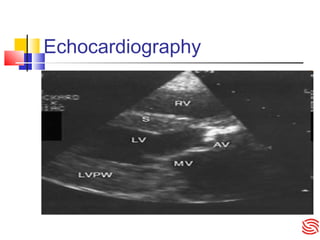

Echocardiography

Further investigations